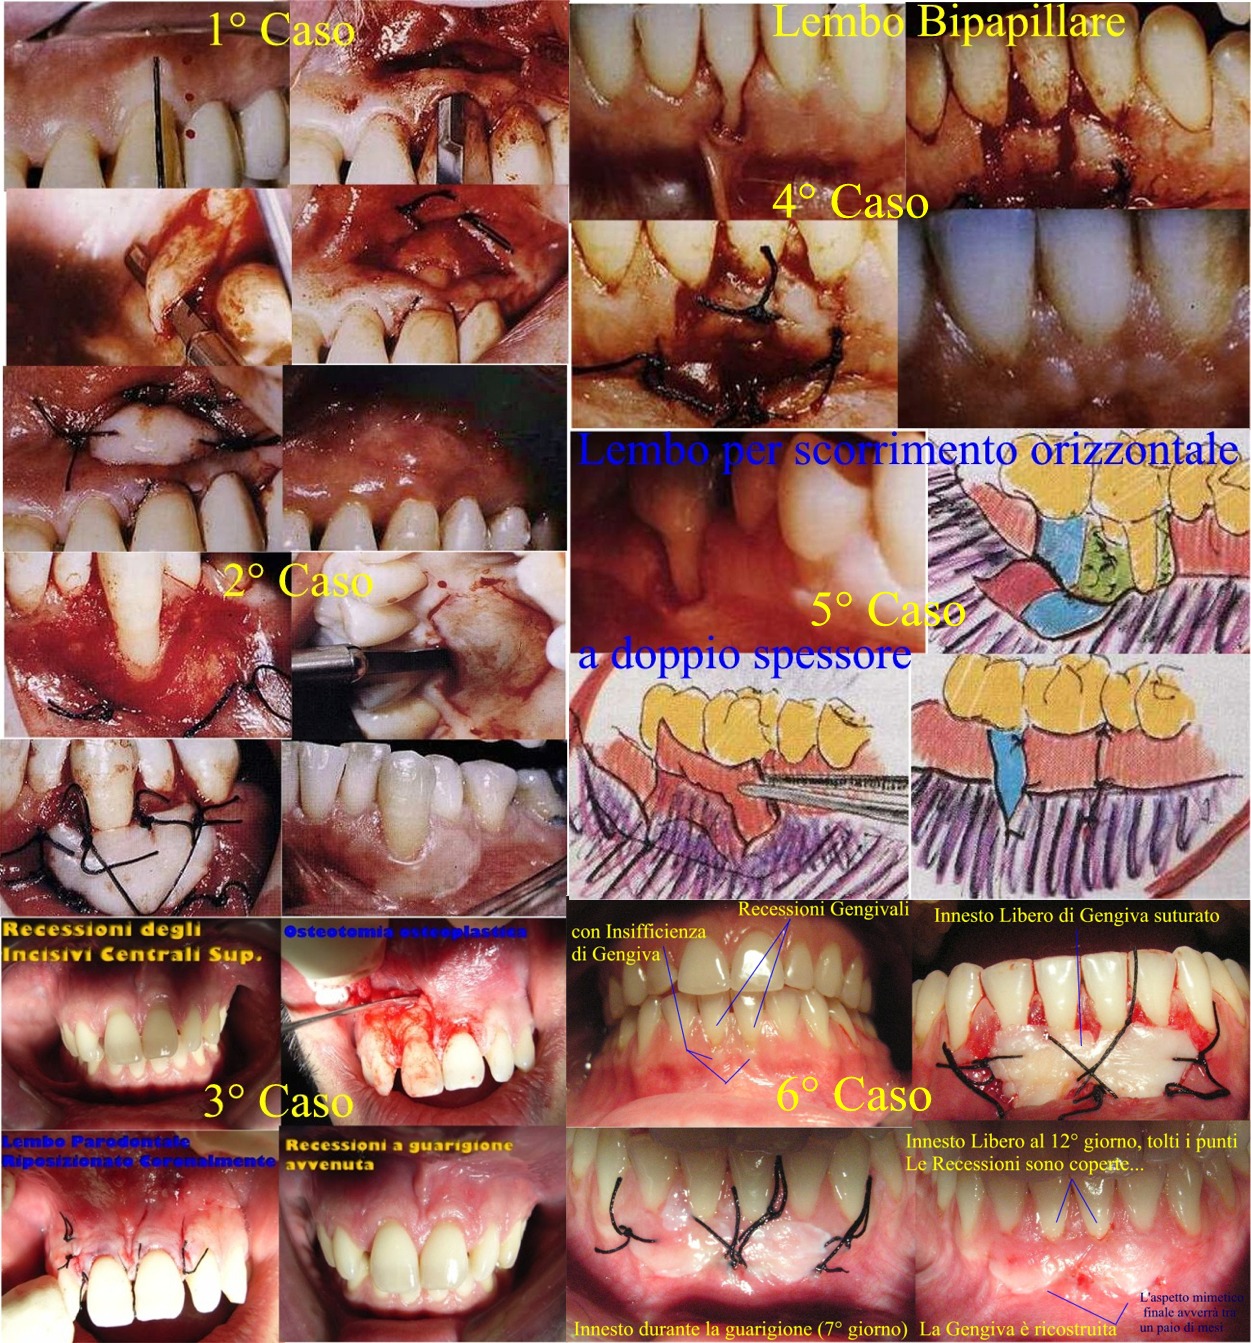

Caro Signor Luigi, buongiorno. Non mi piace che un Paziente mostri questa assoluta mancanza di Rispetto, scritto con la "R" maiuscola apposta per sottolinearne il significato, per il proprio Dentista. Mancanza di Rispetto perché con un colpo di "spugna" ha cancellato in Lei tutta la stima e tutta la Fiducia. Mi domando se ci fossero o se abbia fatto un intervento così importante e delicato, senza avere la minima Fiducia e Stima nel proprio Dentista! Sicuramente l'avrà informata che l'innesto libero di gengiva deve raggiungere due scopi. Il primo è quello Funzionale di ricostruire intorno al dente una quantità sufficiente di Gengiva Aderente, là dove c'è una quantità insufficiente o addirittura assente e il dente sia circondato dalla sola mucosa alveolare che per la sua struttura istologica con un solo strato di cellule e con la sua elasticità e sollevabilità dai piani sottostanti, non può fungere da gengiva marginale adatta al'impatto del bolo alimentare, come invece può e deve fare la gengiva aderente che ha ben sette strati cellulari ed è rigida ed intimamente legata al periostio sottostane e quindi all'osso, con fibre epiteliali che vanno in profondità e fibre connettivali che vengono dalla profondità. Le seconde creano piccole convessità per estroflessione e le prime creano piccole concavità per la introflessione. La loro alternanza crea l'aspetto "a buccia d'arancia" che ha la gengiva sana! Questo obiettivo funzionale è il più importante e deve essere raggiunto per il mantenimento della salute del parodonto. E' stato raggiunto a quanto descrive ed è la sola cosa importante ai fini del successo della terapia di ricopertura della recessione gengivale. Il frenulo è stato escisso o meglio reinserito più apicalmente e anche questo è un risultato funzionale più che apprezzabile. Il secondo obiettivo è estetico e qui ci possono essere dei "problemi" dovuti all'ampiezza e forma della radice da ricoprire perché la radice stessa costituisce un letto ricevente non vascolarizzato ed un innesto può attecchire solo per circa 2 mm sulla superficie radicolare! Dove questa superficie fosse maggiore di 2 mm, l'innesto non potrebbe "attecchire" e si avrebbe una piccola o media o grande a seconda dei casi, recessione iniziale per il formarsi di un profilo concavo. Questo accade non per non bravura del Dentista Parodontologo ma solo per problemi di anatomia chirurgica! Sappia che si può fare un secondo intervento di "sollevamento" tipo "tendina" della Gengiva innestata per ottenere anche l'estetica. Oppure esistono altri interventi di completamento del primo come lembi cosiddetti a busta con innesto solo connettivale e tanti altri di tanti tipi per curare anche l'estetica, se ovviamente fosse possibile e ci fossero le condizioni anatomiche per poterli fare. Legga nel mio profilo le numerose pubblicazioni scritte sulle recessioni gengivali quali "Recessioni Gengivali : Lembo semilunare" e "RECESSIONI GENGIVALI : Lembo Riposizionato Lateralmente" e "RECESSIONI GENGIVALI: LEMBO CON DOPPIA PAPILLA (Bipapillare secondo tecnica di Goldman), in una grave terza classe di Miller" ed ancora "RECESSIONI GENGIVALI : Innesto libero di gengiva" e tanti altri tra cui quello che potrebbe essere utile a lei "RECESSIONI GENGIVALI: Trattamento chirurgico con lembo a riposizionamento coronale e innesto libero di gengiva". Lo dico da Parodontologo quale sono. Non disprezzi il risultato ottenuto dal suo Dentista, le ho spiegato perché. Parli con lui delle varie soluzioni chirurgiche di completamento estetico dell'intervento. Legga anche nel mio profilo "La chirurgia parodontale estetica Introduzione Divulgativa alla Chirurgia Estetica Parodontale"! Le lascio un Poster di interventi di Chirurgia Mucogengivale per la terapia delle recessioni tra cui anche innesti iberi di gengiva aderente (li vedrà in basso soprattutto).C'è bisogno di avere conferme sul Web anziché chiedere al suo Dentista? Si affidi al suo Dentista con più Fiducia e Stima e Rispetto, che diamine! Il rapporto di Fiducia e Stima reciproca Medico-Paziente è fondamentale e se venisse meno, verrebbe a mancare il presupposto più importante per fare o continuare una terapia! Non trova corretto quanto dico :) ? Se questa è la terapia prospettata, questa deve fare e se avesse come ha, l'animo di "dissentire", deve parlarne con il suo Dentista. Se scoprissi mai che un mio paziente si comportasse con me, come ha fatto Lei con il suo Dentista, mi rifiuterei di proseguire la cura perché la Stima e la Fiducia oltre che il Rispetto, sono essenziali nel rapporto Medico-Paziente e venute meno queste come nel suo caso, non avrebbe più motivo dell'esistenza di questo rapporto e quindi della cura! Per concludere, il risultato immediato è quello di ottenere un successo FUNZIONALE ; quello invece ESTETICO, si può ottenere al 100% o in percentuali minori fino a percentuali bassissime a seconda della situazione Clinica ed anatomica ma esistono poi interventi per migliorare l'estetica fino al 100%, se possibile. Incominci a seguire intanto i suggerimenti sapienti del suo Dentista, poi si rivaluterà il tutto a guarigione terminata che impiega circa 4-24 mesi ad arrivare! Per inciso, la "barriera protettiva ( tipo pongo )" di cui parla non è altro che l'impacco parodontale e così va chiamato! Cari saluti